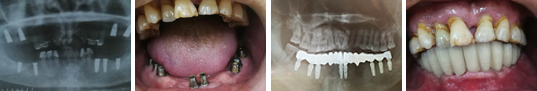

开展人工种植牙应有配套的种植牙设备和材料的医院或诊所,由经过人工种植牙专业培训的医师和义齿制作技师进行。 目前我市开展人工种植牙工作清花园口腔门诊是最早的,并获市新技术应用三等奖。

清花园口腔门诊具有全套高品质德国人工种植牙设备和材料:采用德国设计生产的国际上最 先进的人工种植牙系统。拥有高素质的人工种植牙团队。种植牙医师和义齿加工技师都多次 接受德国著名专家的高级培训。已完成的人工种植牙病例,可以达到国际先进水平。获市新技术应用三等奖。